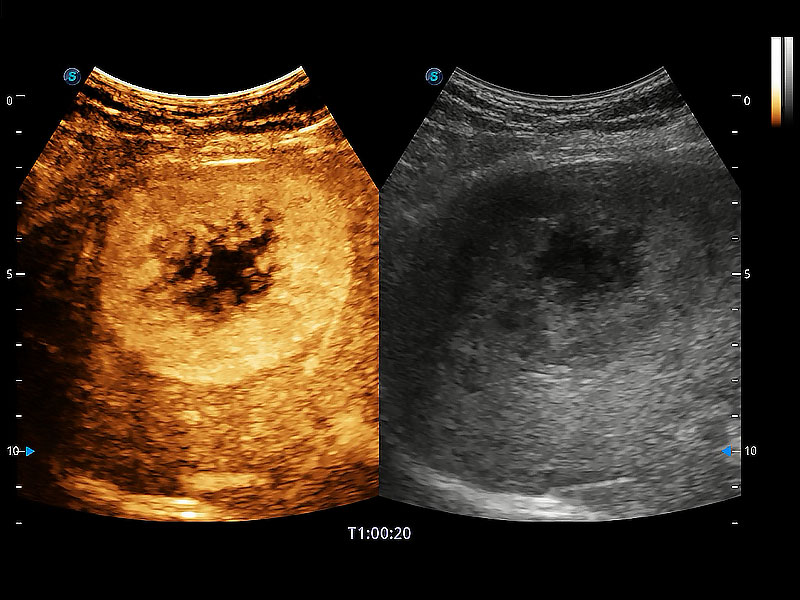

(犬)肝脏

(猫)胆囊

(犬)肾脏显微血流